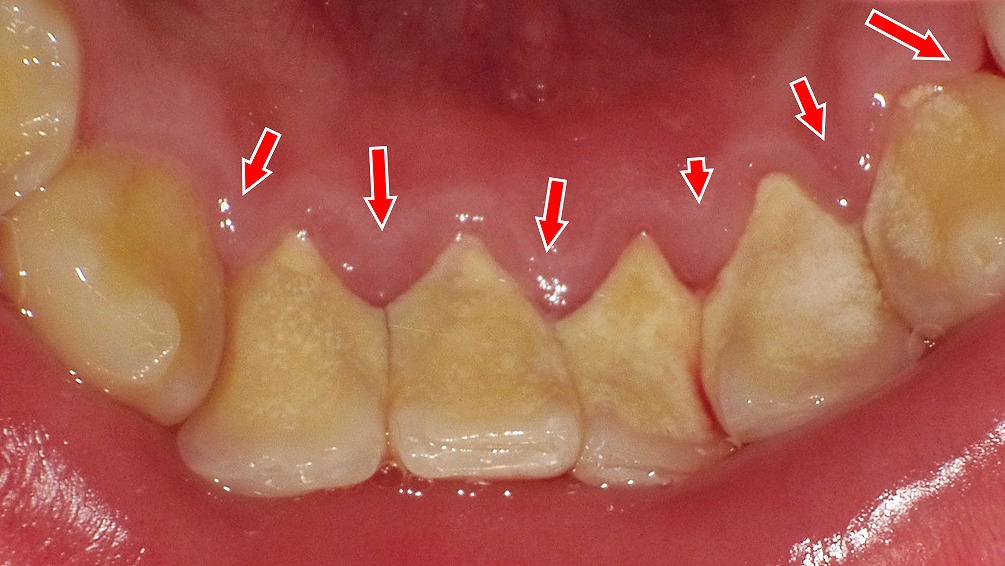

歯石除去前後でわかる歯ぐきと全身への影響

歯石が付着し歯肉が腫脹している状態(治療前)と、歯石除去後を示した同一症例です。歯周病による慢性的な炎症は、歯周病菌や炎症性物質が血流に乗って全身へ広がり、動脈硬化や心血管疾患のリスクを高める可能性があるとされています。歯石除去を中心とした歯周治療は、歯を守るだけでなく、全身の健康を考えるうえでも重要な治療です。